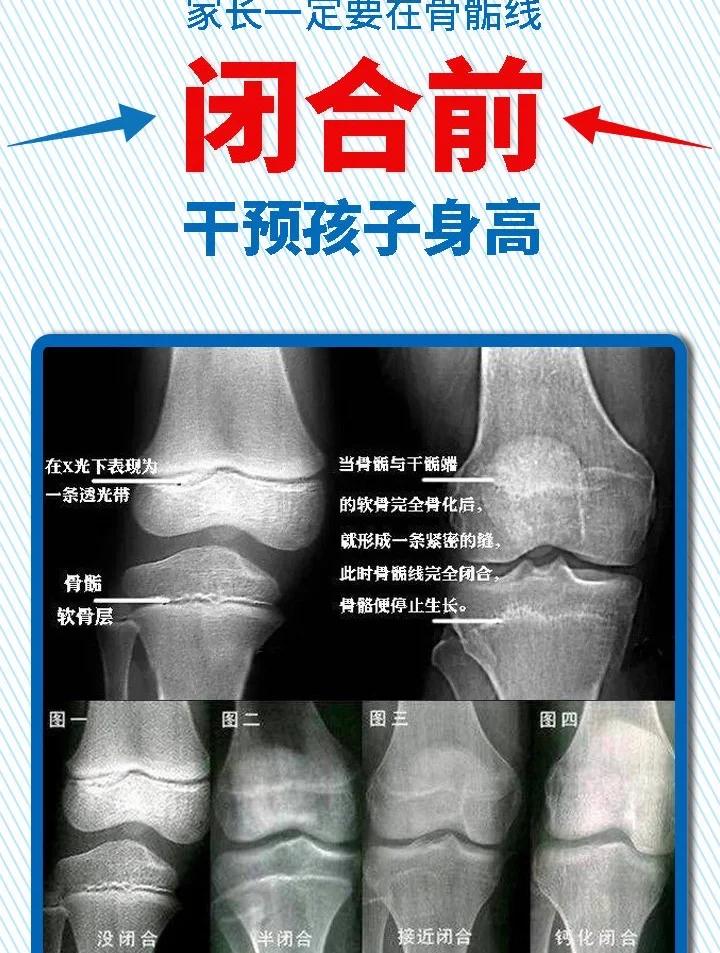

骨骺线闭合与长高的关系骨骺线是骨骺和干骺端之间的软骨,在X光片上表现为透光带随着年龄增长,骨骺线逐渐钙化,完全骨化后,长骨不再生长,四肢不再变长,人体也就没有长高空间女性骨龄在17 25岁,男性骨龄在18 27岁时,骨骺线会逐渐闭合,生长几乎终止,不过闭合时间因人而异骨骺线。